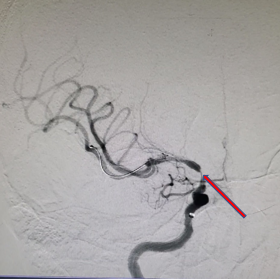

急诊DSA检查。

导丝怎么扩【载药时代 球扩天下】NOVA DES®颅内药物洗脱支架在颈内动脉颅内段重度狭窄的应用两例!滕州市中心医院&山西医科大学第二医院_https://www.jmylbn.com_新闻资讯_第4张

重要影像结论:左侧颈内动脉后交通段闭塞。

DSA:右侧颈内动脉正侧位

重要影像结论:右侧颈内动脉C6段狭窄约90%,长度约0.97cm。

治疗中影像

治疗中路径显示患者右侧颈内动脉的迂曲。

导丝怎么扩【载药时代 球扩天下】NOVA DES®颅内药物洗脱支架在颈内动脉颅内段重度狭窄的应用两例!滕州市中心医院&山西医科大学第二医院_https://www.jmylbn.com_新闻资讯_第16张

导引导管到位,导丝通过病变。

导丝怎么扩【载药时代 球扩天下】NOVA DES®颅内药物洗脱支架在颈内动脉颅内段重度狭窄的应用两例!滕州市中心医院&山西医科大学第二医院_https://www.jmylbn.com_新闻资讯_第17张

球囊通过病变扩张血管后,残余狭窄30%,局部血管夹层可疑。远端通路导管在球囊导管的引导下通过迂曲的C3、C4段,抵达病变血管近端。